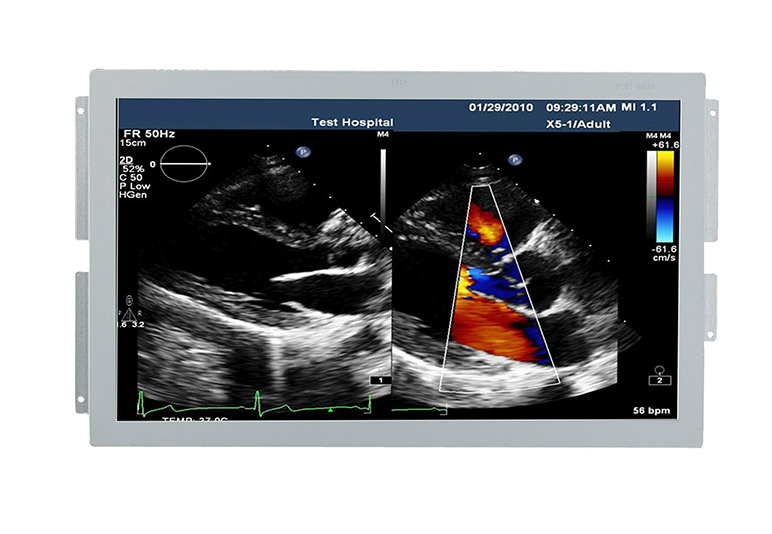

и¶…еЈ°еҢ»з”ЁжҳҫзӨәеҷЁ